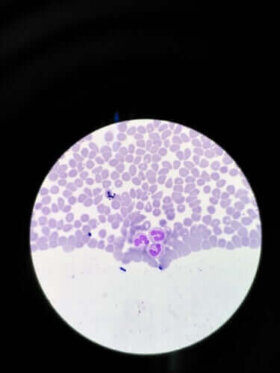

과립구 감소증은 과립 백혈구가 너무 낮아진 상태를 말한다. 이 혈액 질환은 또한 호중성 백혈구 감소증 또는 과립백혈구 감소증이라고도 불린다. 가장 널리 알려진 정의에 따르면, 호중구 수가 혈액 1입방밀리리터당 1,000~1,500개 미만인 경우에 발생한다. 전반적으로 호중구, 산호성백혈구 및 호염기성세포, 이렇게 3종류의 과립구가…